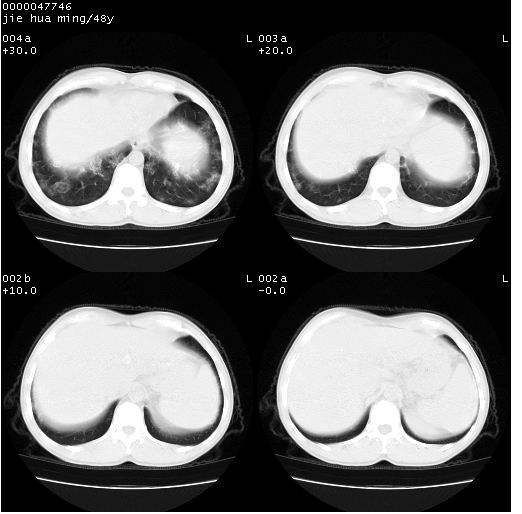

以下是引用dr.yang在2008-5-1 6:25:00的发言:[br]两肺广泛毛玻璃样的片状影,密度不均,边缘欠清,呈碎石路样改变,[br]考虑,1双肺间质性肺炎,2肺泡蛋白沉积症3支气管肺泡癌[br]

以下是引用hhcckk在2008-5-1 8:06:00的发言:[br]支持肺泡蛋白沉积症[br]依据:[br]1、病灶边缘清楚----地图征[br]2、病灶内部小叶间隔或小叶内间隔增厚所形成的网格状影----碎石路样表现[br]3、抗炎治疗无效(炎症抗炎治疗有效)[br]4、纵隔内未见肿大淋巴结(肺泡细胞癌时常有)[br][br]附肺泡蛋白沉积症资料[br][br]肺泡蛋白沉积症(pulmonary alveolar proteinosis)是一种原因不明的以肺泡腔内大量含脂糖蛋白样物质沉积为特征的疾病。[br]病理改变:(1)肺泡和细支气管腔内充满大量含脂糖蛋白样的粘稠物质,该物质为颗粒状或絮状的糖原pas染色阳性的磷脂蛋白。(2)肺泡壁及其间隔无异常改变。胸膜和淋巴结不受累及。(3)晚期可出现弥漫性肺间质纤维化。[br]临床表现:(1)好发年龄30~50岁,男性多于女性,偶见于儿童;(2)主要症状为呼吸困难、咳嗽、低热、消瘦、低氧血症和杵状指等。1/3的患者无症状。(3)实验室检查:痰液或肺泡灌洗液中可找到pas染色阳性颗粒物质。[br]hrct表现:肺泡蛋白沉积症具有特征性改变,即“碎石路样”表现(crazy-paving appearance,cpa)。主要包括(1)斑片状磨玻璃影:指肺野密度朦胧增加,内可见肺血管纹理影,系肺泡腔内充满低密度的磷脂蛋白物质所致。(2)其内部小叶间隔或小叶内间隔增厚所形成的网格状影,为小叶间隔水肿、肺泡壁内淋巴细胞和巨噬细胞浸润以及小叶内淋巴管扩张的缘故。(3)病灶边缘清楚,呈地图样分布于肺野外围或肺门及中央区。[br]

以下是引用zsl6918在2008-5-1 7:35:00的发言:[br]双肺磨玻璃样病变,可见铺碎路石征,病变区与正常区交错。边界清晰。符合肺泡蛋白质沉着征,高分辨扫描会更清楚漂亮。建议临床肺泡灌洗。

以下是引用yangyudong333在2008-5-1 5:36:00的发言:[br][br] 两肺广泛毛玻璃样的片状影,密度不均,边缘欠清,呈碎石路样改变,[br]考虑,1双肺间质性肺炎,2肺泡蛋白沉积症[br]